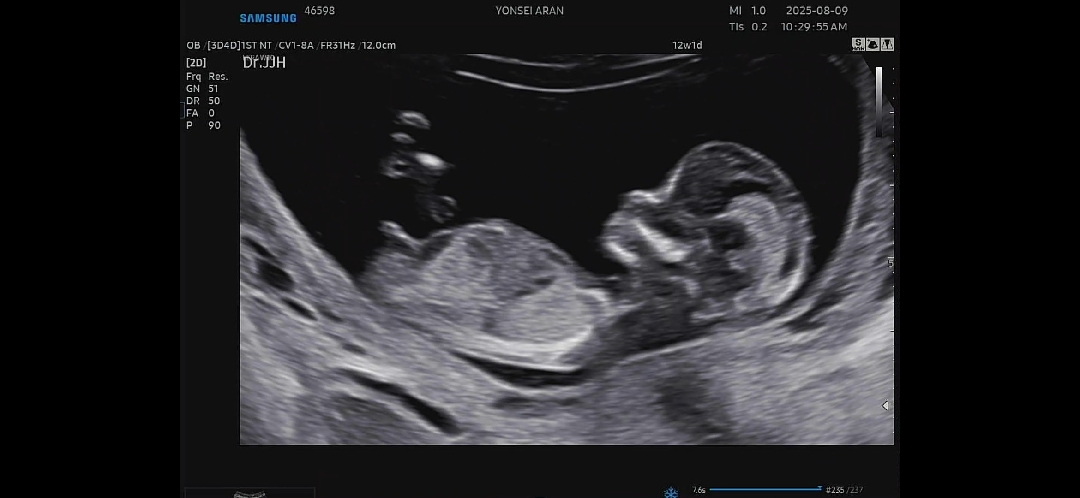

성별 봐주세요😌🥹

12주2일차